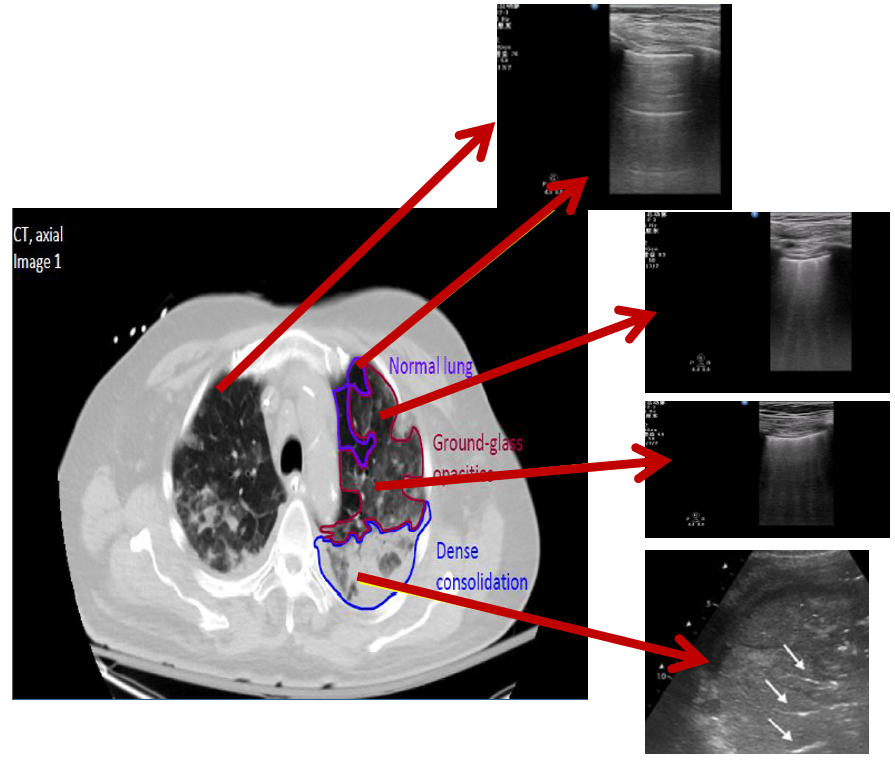

(5)ARDS:ARDS的超声征象特点是根据不同区域的病理改变,从前侧到后侧会出现正常通气的A线以及磨玻璃样变、肺水增多的B线以及偏后部的C征象。

图片